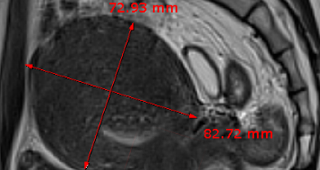

자궁근종 비수술 하이푸 치료 후 임신분만사례입니다. 아직 자녀가 없으신 분으로 복부에 만져지는 증상으로 자궁근종 하이푸 치료를 위해 내원하였습니다. 하이푸 시술전 MRI 사진상 자궁은 7.5cm 크기로 자궁전벽의 ...